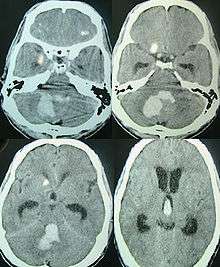

Intraparenchymal hemorrhage can be recognized on CT scans because blood appears brighter than other tissue and is separated from the inner table of the skull by brain tissue. The tissue surrounding a bleed is often less dense than the rest of the brain because of edema, and therefore shows up darker on the CT scan.[14]